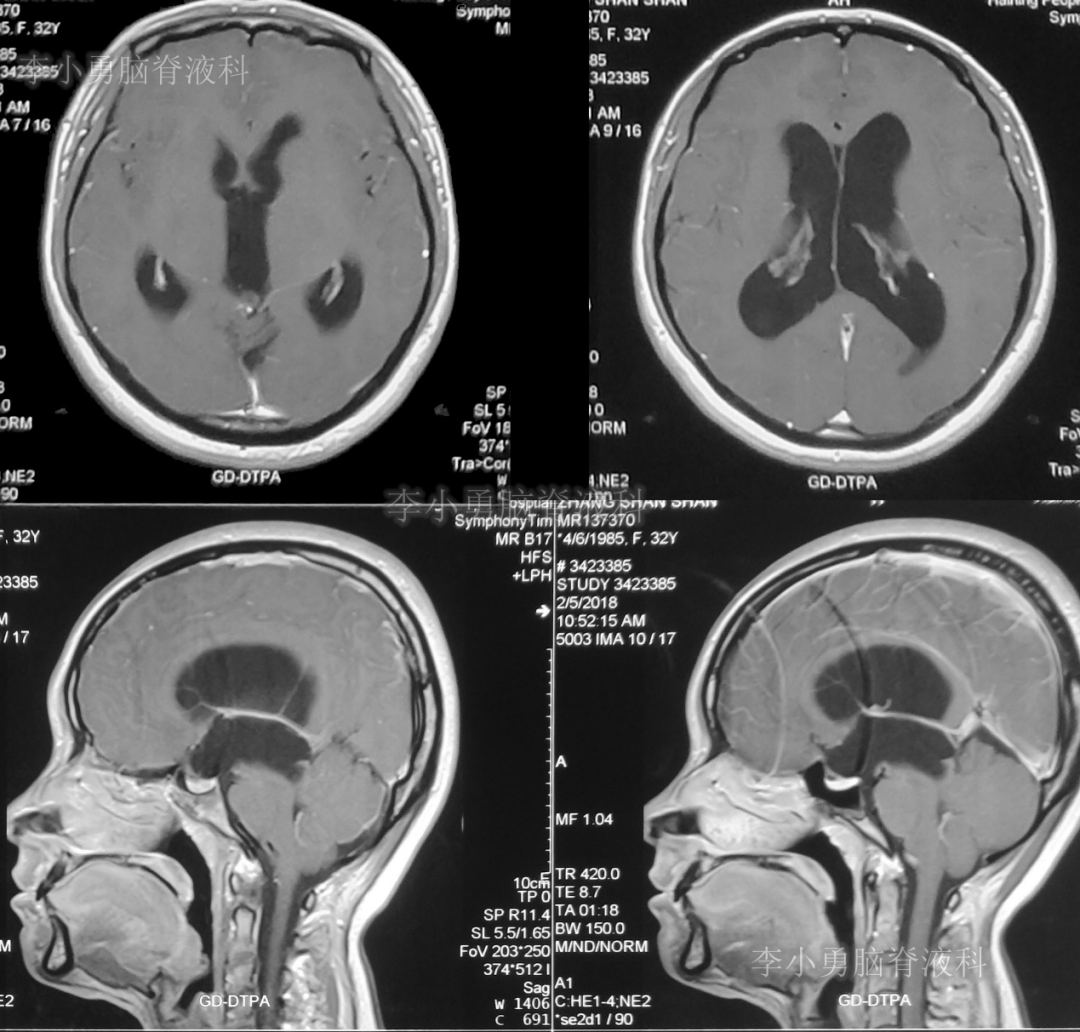

又2天后,即2018年2月5日,为求更好的治疗,患者转到第2家医院:浙江省杭州市的某三甲医院就诊,行头颅增强核磁共振检查(图-2)提示双侧脑室及第三脑室扩张,中脑导水管形态消失,第四脑室无扩张,未见颅内占位病变。

图-2:2018年2月5日头颅核磁